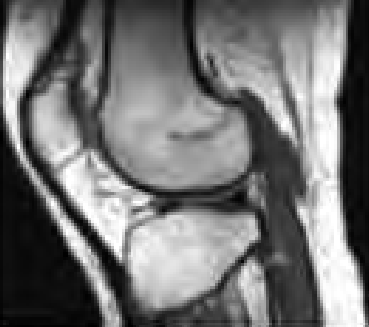

Wskaż przyczynę powstania artefaktu widocznego na obrazie MR.

Ilustracja do pytania 25

A. Wymiary obiektu przekroczyły pole widzenia.

B. Niejednorodność pola magnetycznego.

C. Nieprawidłowa kalibracja aparatu.

D. Błędny dobór cewki gradientowej.